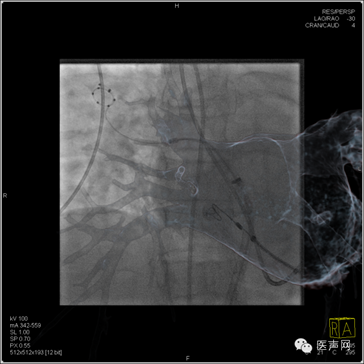

影像融合下用于冷冻球囊的定位

右上肺静脉消融补点及起搏验证,可于X线直视下展示消融导管头端与CT影像的空间相关性

牛国栋教授介绍到:在进行房颤冷冻球囊消融时,在X线造影下观察到的只是平面投影结构。由于肺静脉和心脏结构的复杂性,在进行导管操作时,往往会出现一些困难。结合影像融合技术,可以三维地呈现肺静脉分叉情况和心房结构,能指引导管操作、球囊定位,缩短进入肺静脉的时间即X线曝光时间,从而进一步降低射线量。随着这项技术的不断探索完善,我认为对于CRT植入术、左心耳封堵术、冷冻球囊消融术等有一定帮助。